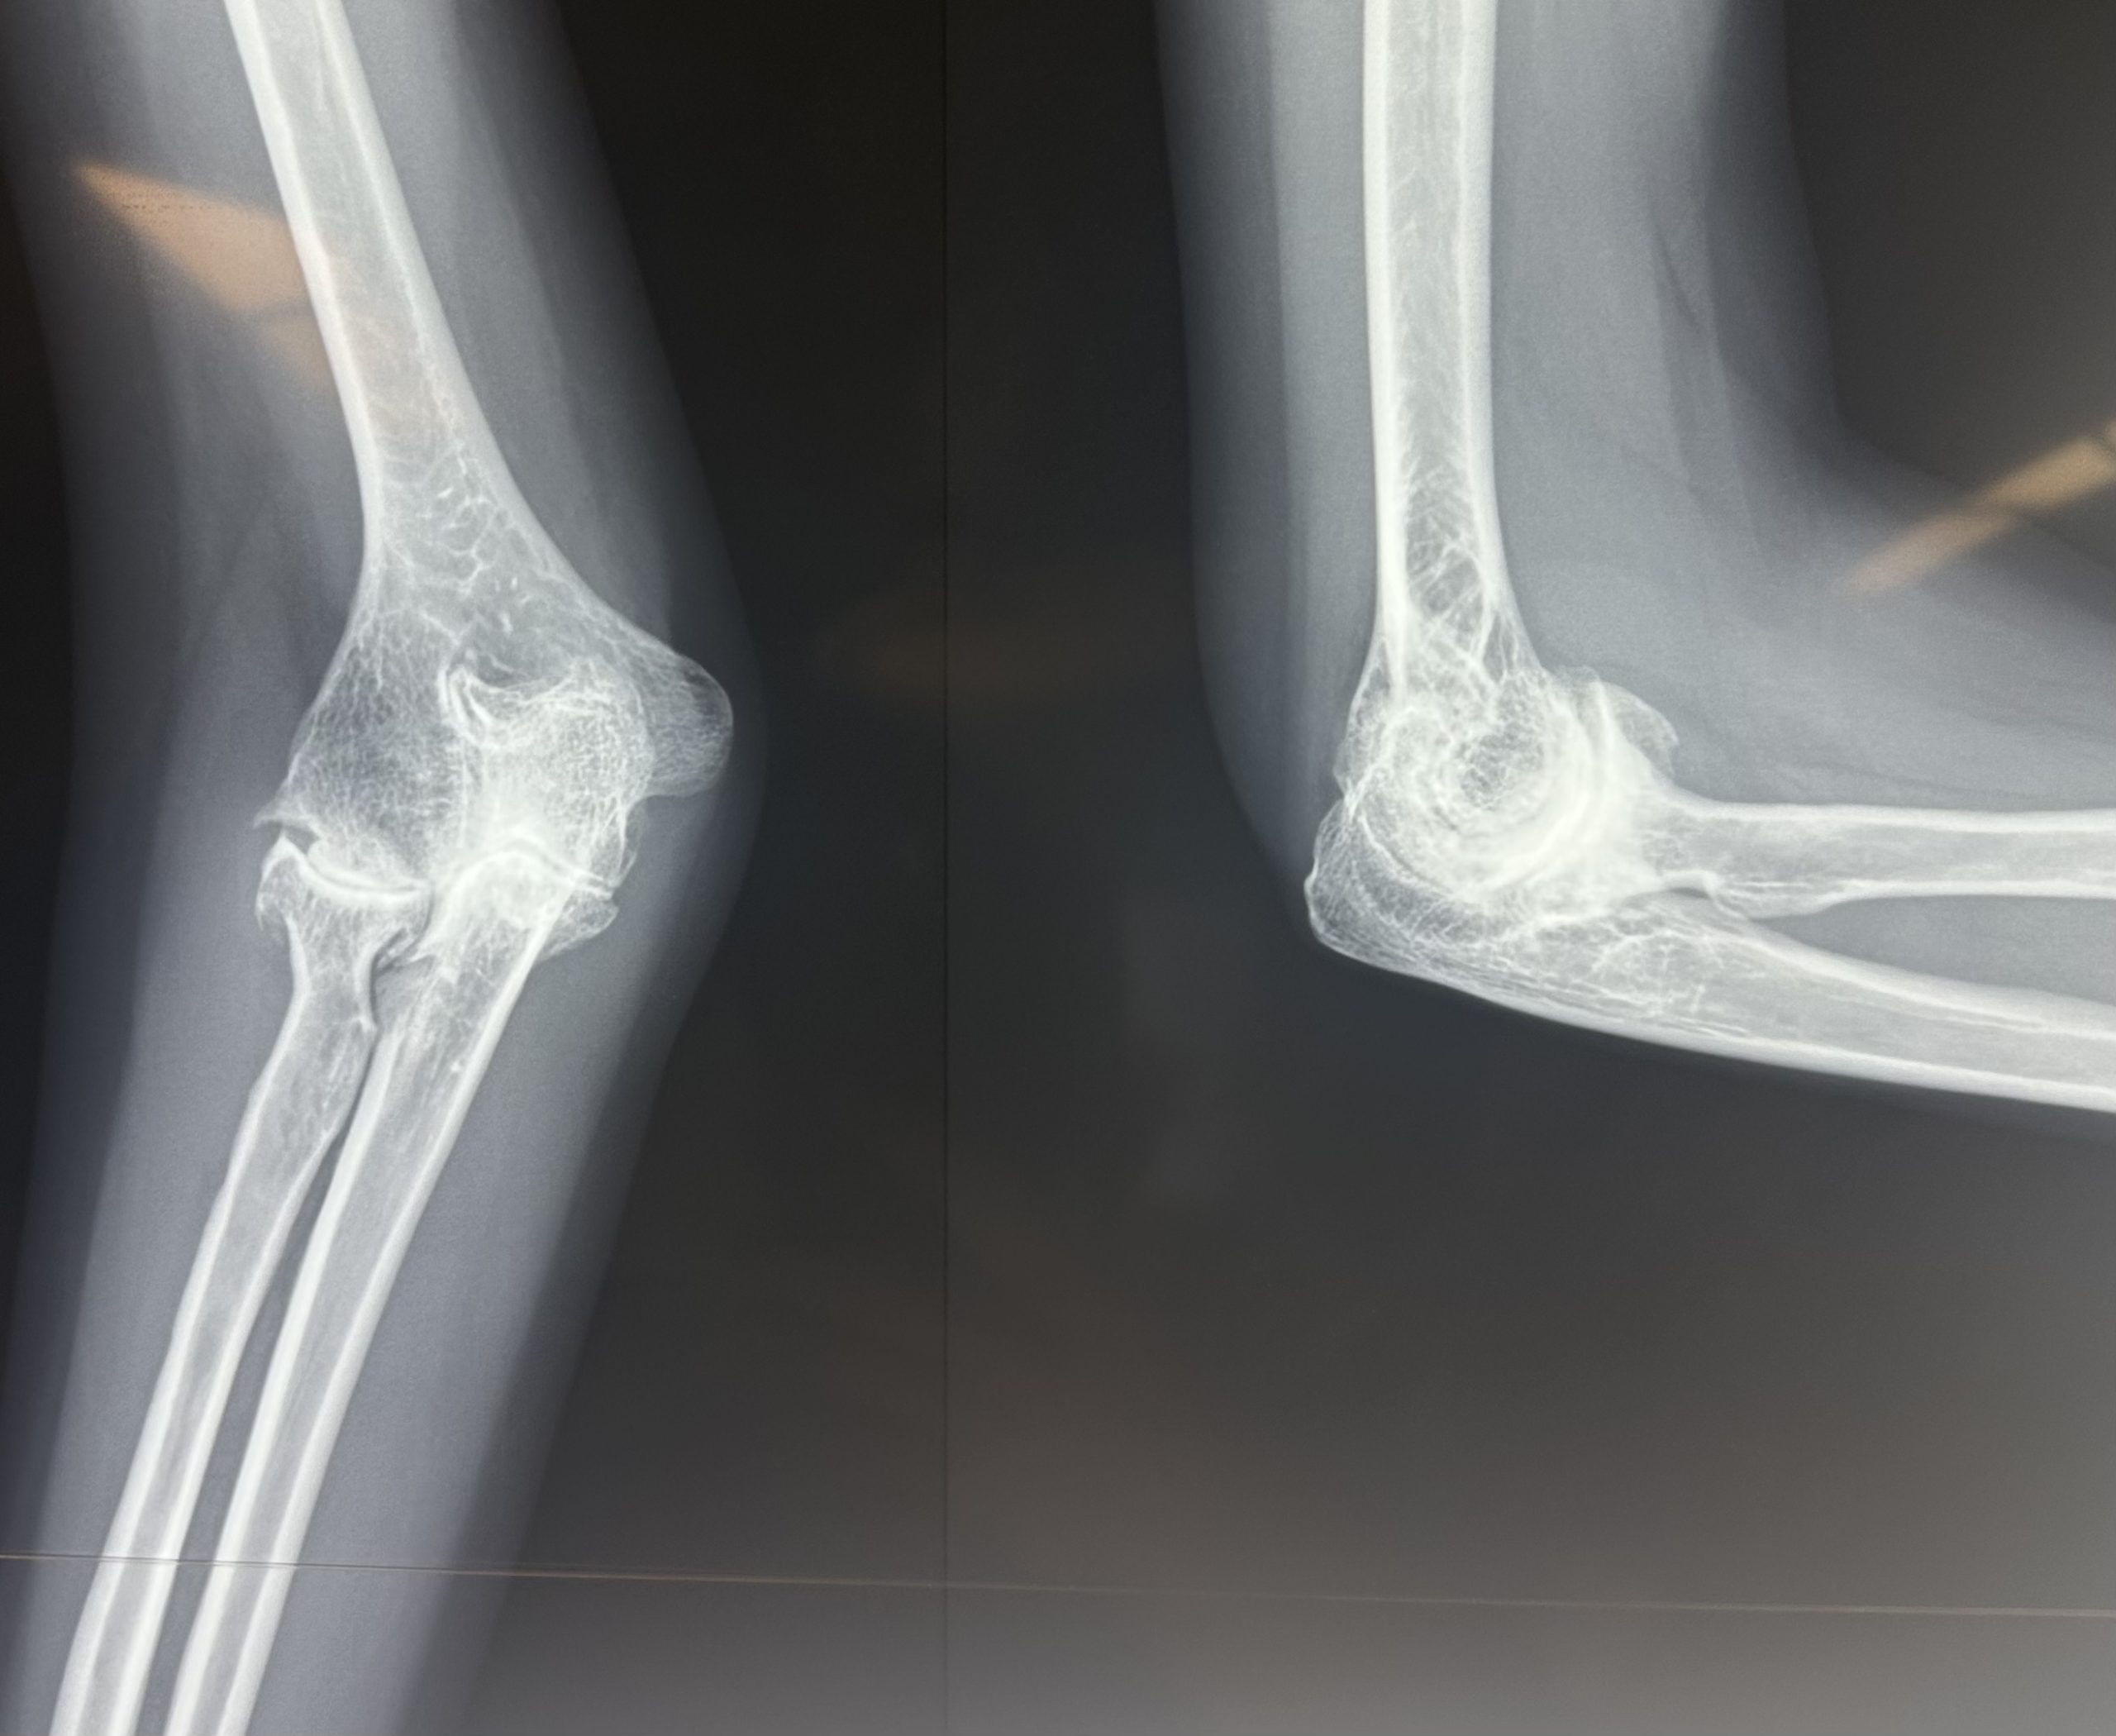

- Plain X-ray: AP and lateral views. Shows osteophytes at olecranon tip and coronoid process, loose bodies, joint space narrowing in advanced disease

Elbow osteoarthritis is less common than hip, knee, or shoulder arthritis because the elbow carries predominantly compressive rather than shear loads during most daily activities. However, it causes significant disability when it does occur — particularly in heavy manual workers and throwing athletes who have subjected the joint to decades of high loading. Primary elbow OA most commonly affects dominant-arm manual workers (miners, blacksmiths, heavy machine operators) and is characterised by osteophyte formation at the olecranon tip and coronoid process, rather than the diffuse joint space narrowing seen in other joints.

Primary Osteoarthritis | Degenerative cartilage loss — dominant arm heavy manual workers. Osteophytes at olecranon/coronoid tips cause terminal flexion and extension block. Joint space relatively preserved until late. |